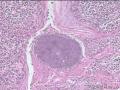

扁桃体隐窝菌落?

性别

男

年龄

9岁

打鼾两年余

扁桃体

扁桃体组织

扁桃体隐窝是菌落吗?

放线菌